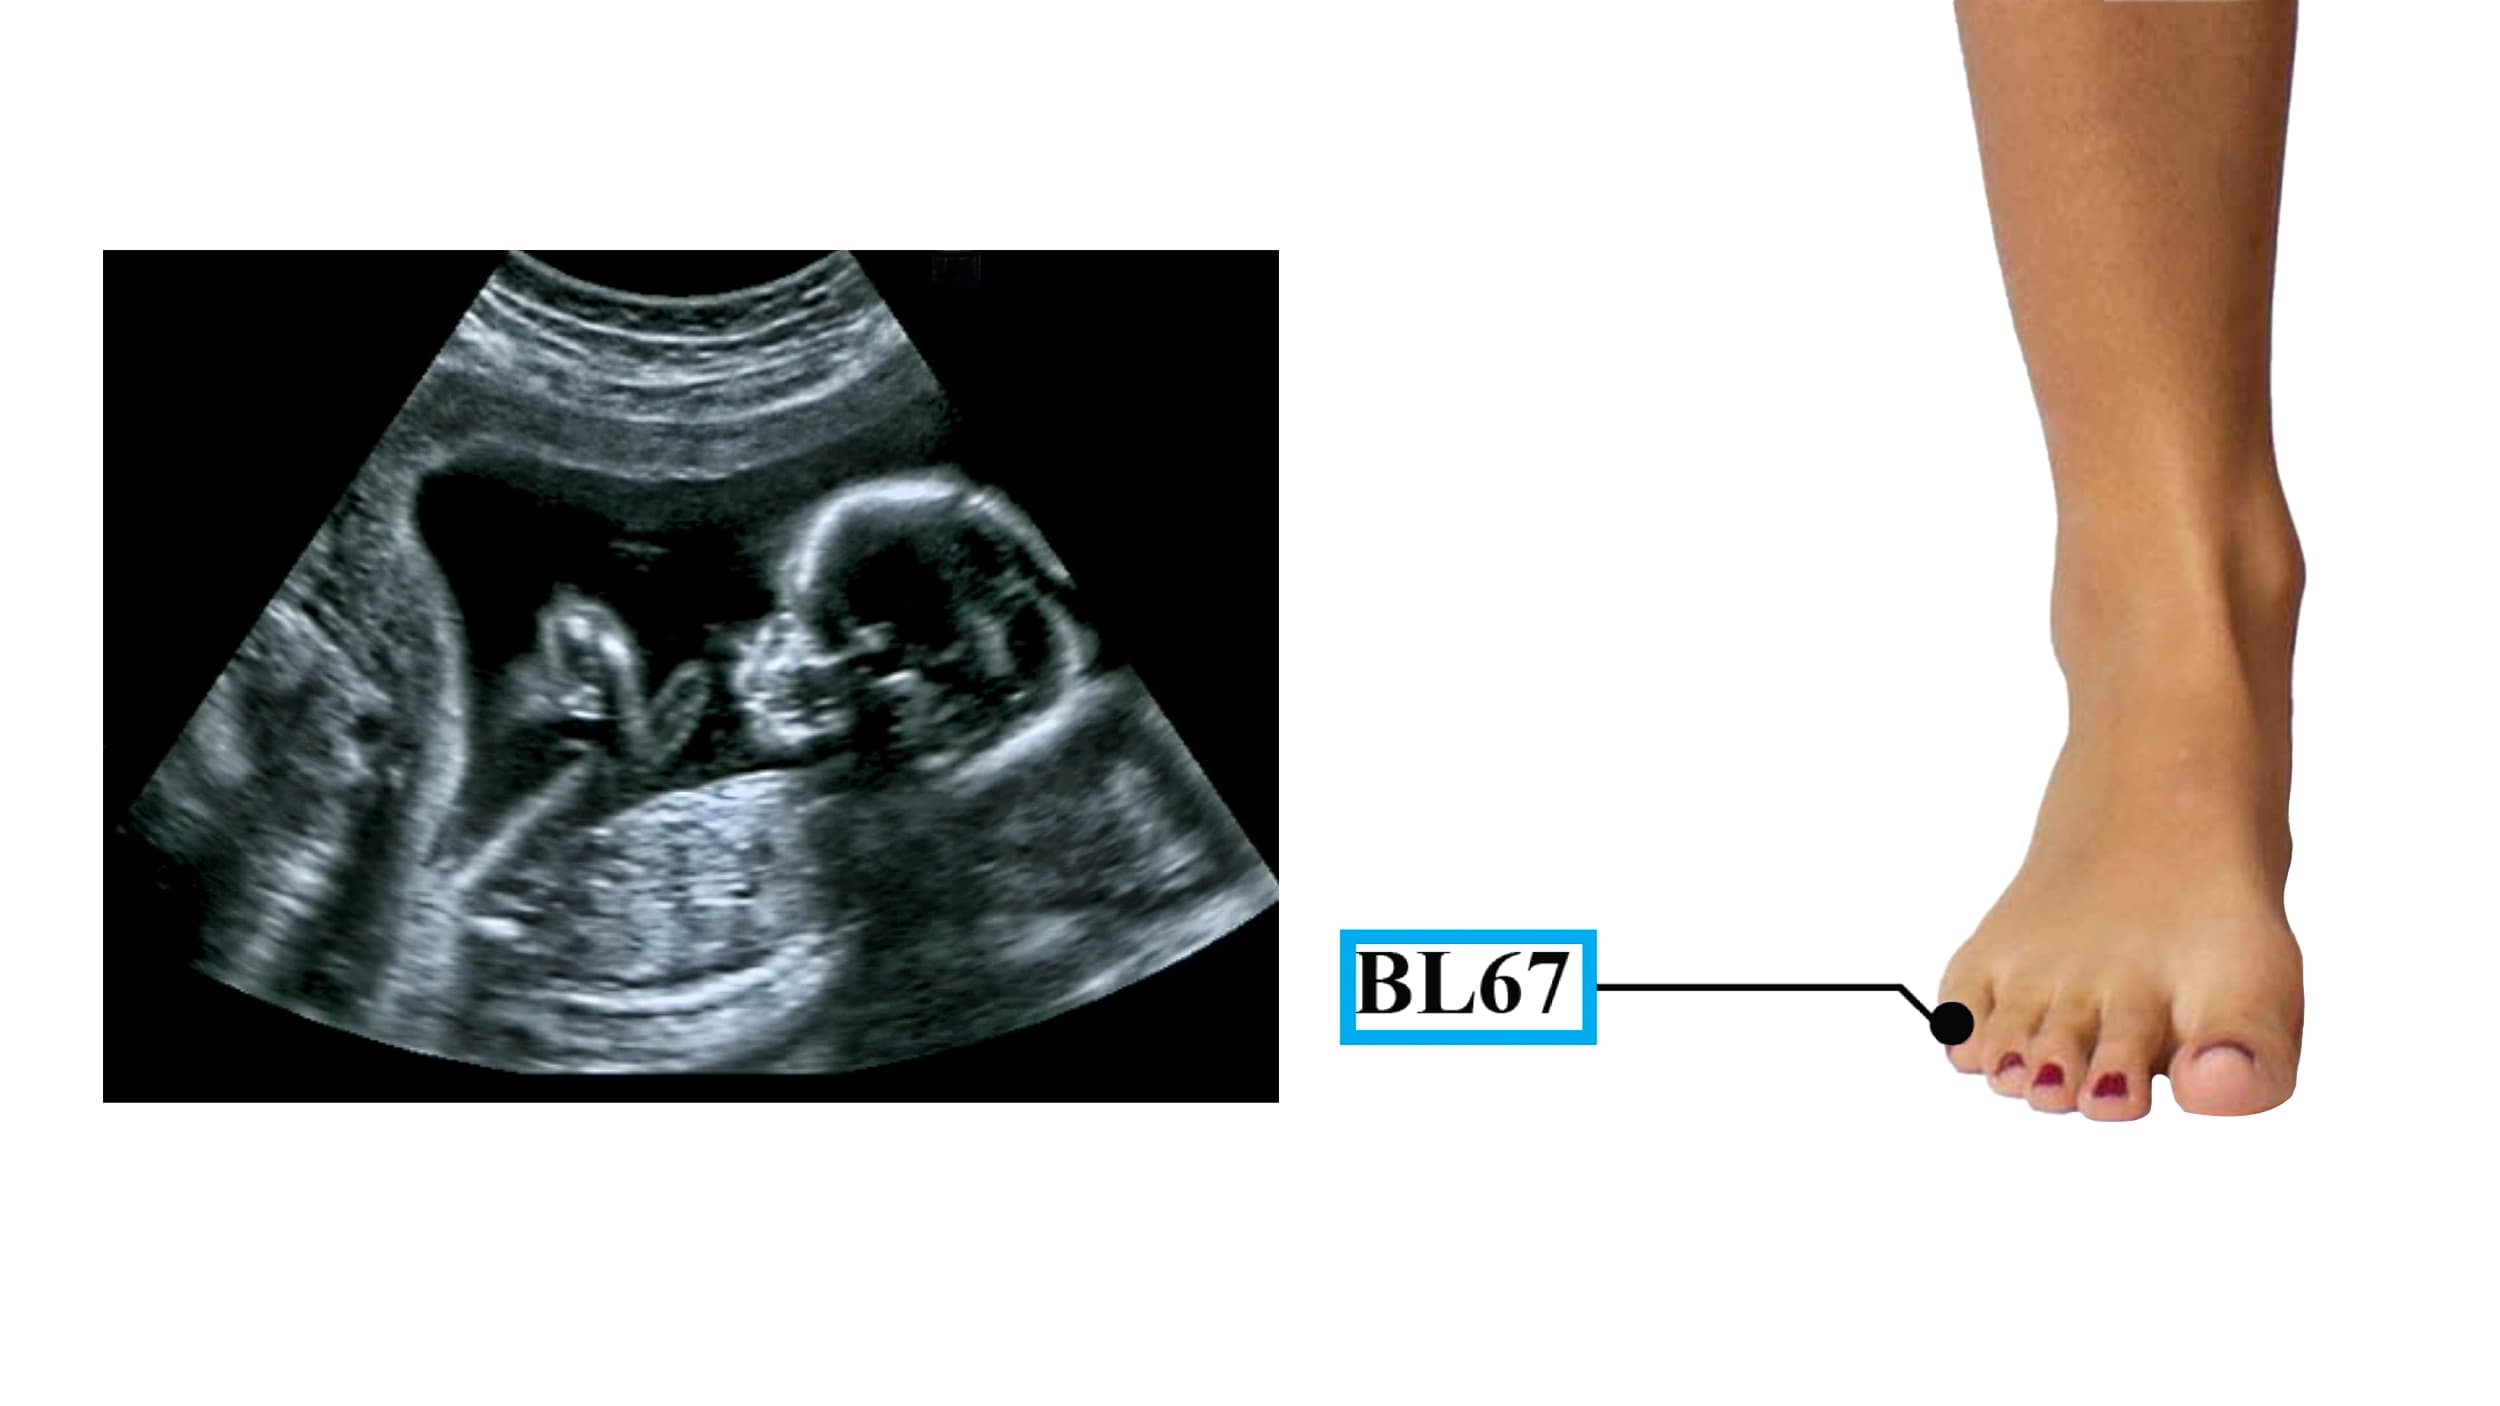

L’esperimento condotto sul punto zhiyin (BL67)

Studio: 90,32% dei Casi

Trattamento della posizione anomala del feto

L’esperimento condotto sul punto zhiyin (BL67), corregge la posizione anomala del feto al termine della gravidanza con l’applicazione della Moxibustione, riscaldando il punto tramite bastoncino ardente di artemisia. 2069 casi trattati e una percentuale di successi del 90,32% illustrata a Pechino nel 1979, durante il Simposio Nazionale dell’Agopuntura e della Moxa dal team del professor Wang Wen Shih. L’esperimento non mostra effetti di natura neurovegetativa simpatica, ma un netto incremento della secrezione ormonale in corrispondenza del 17-idrossidocorticosterone, 17-chetosteroidi e del cortisone plasmatico. Tali effetti sono imputati a un’azione sul sistema ipofisario-surrenale e sono più evidenti nelle donne gravide. Per dimostrare la specificità di questo punto, venne ripetuta l’esperienza stimolando con la Moxibustione la punta del pollice anziché quella del mignolo, in questo caso non si verificò alcuna variazione ormonale, nè alcun effetto sul feto.